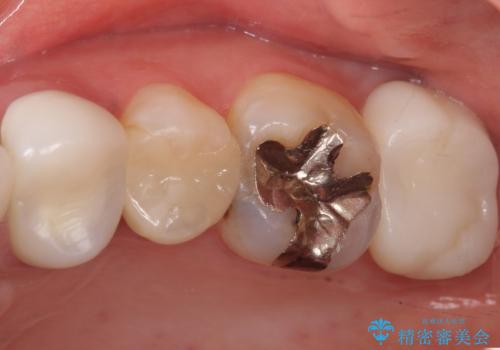

かぶせ物の種類:Bellezza screw retain

- 単独のインプラント補綴にて咬合の回復を計画した。